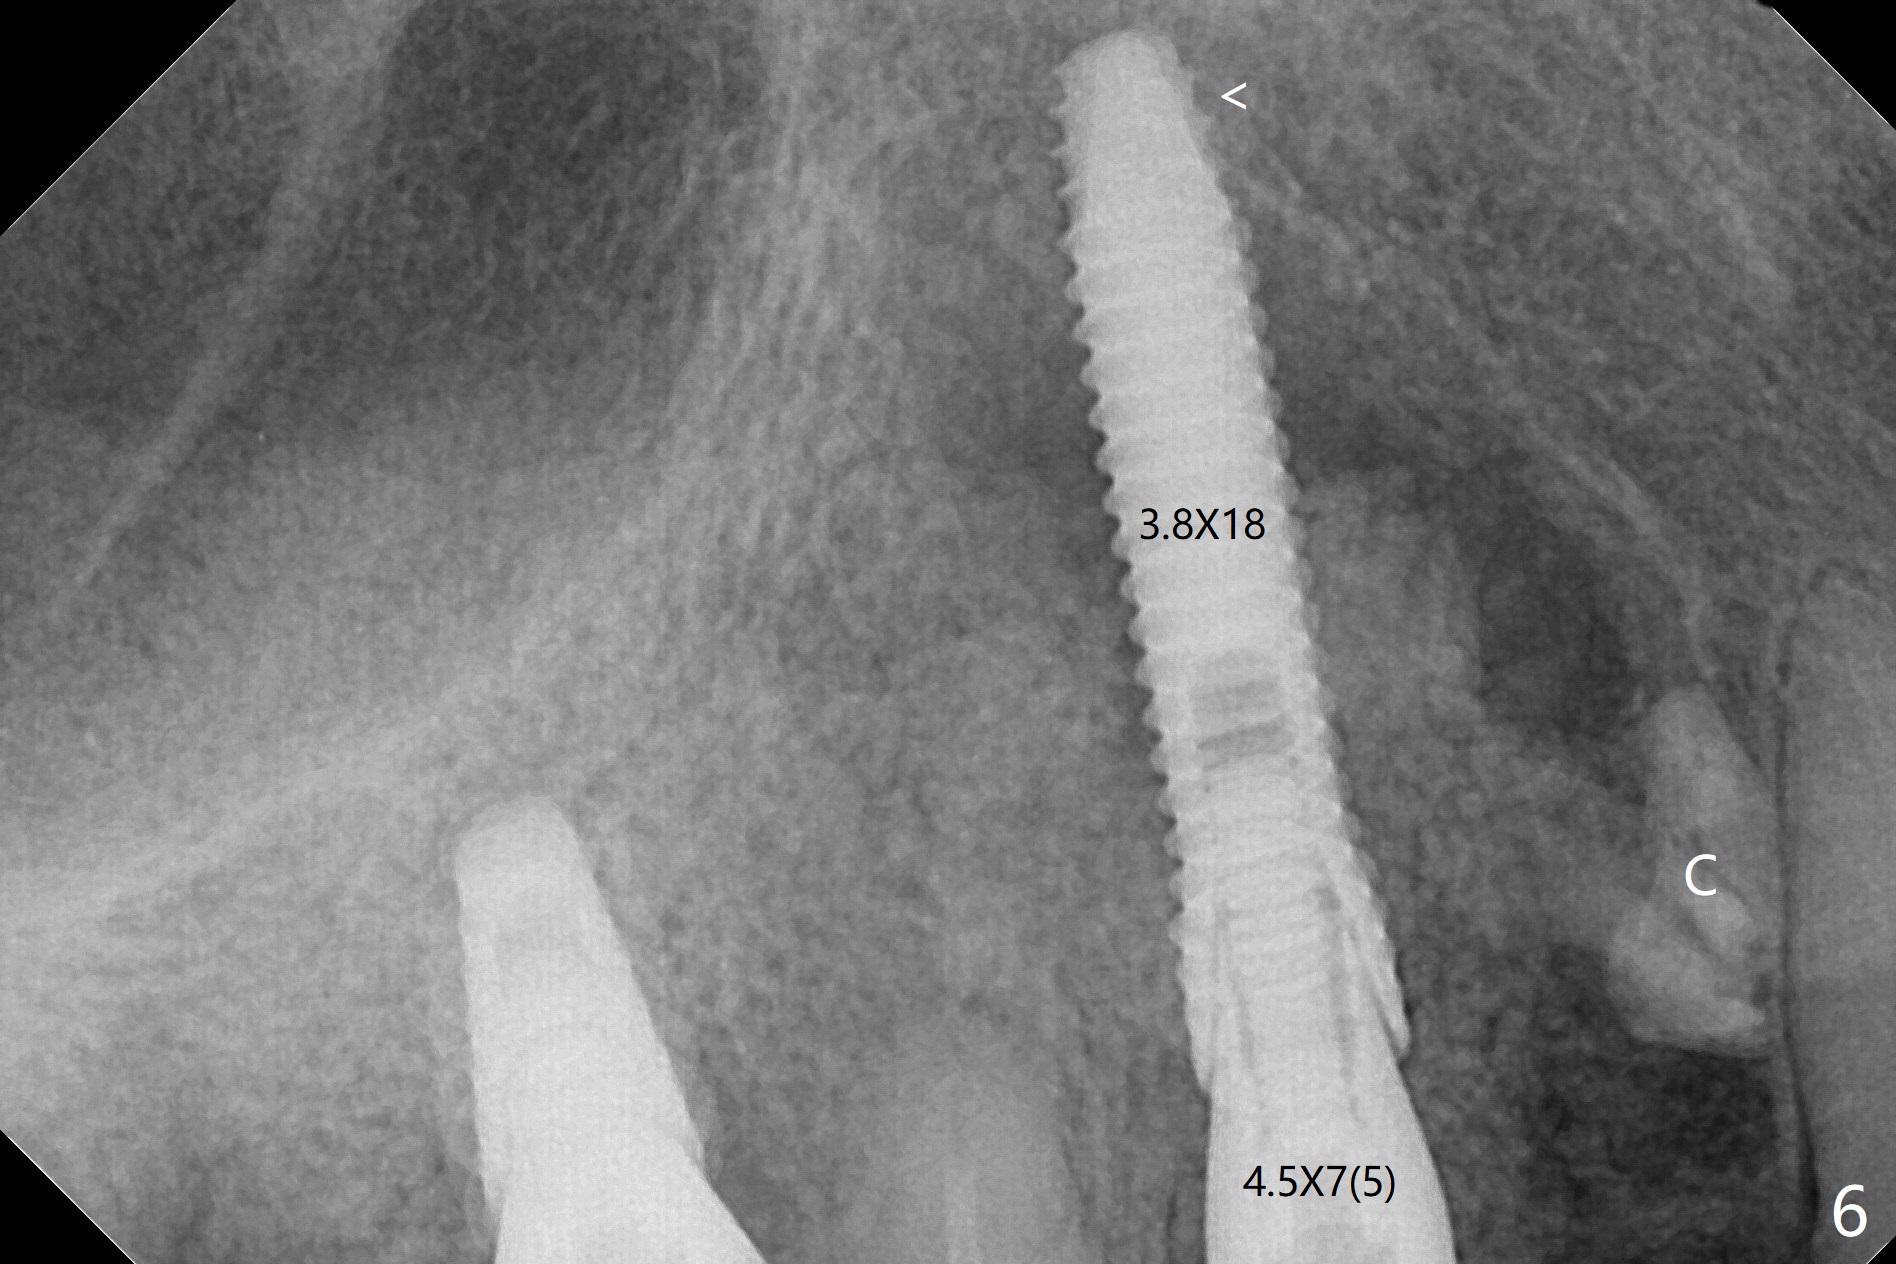

After incision and flap elevation, the crown of the impacted canine is more superficial. With removal of the buccal cortical plate and multiple sectioning of the crown, the latter is removed (Fig.1 *). Further removal of the buccal plate (P) and purchase points, the root (R) is extracted easier. In fact the apex of the root is the deepest (Fig.2). With the guide (Fig.3 G) and 2.2 mm drills, the osteotomy is established. It is pretty shallow. A 3x18 mm drill is used to deepen the osteotomy free hand (mistake: too palatal). When a 3.8x18 mm UF implant is being placed, it cannot be placed deep with the guide. When the latter is removed, the implant seems to be placed too deep and too buccal with <10 Ncm (Fig.4). A 4.5x7(5) mm abutment is placed mainly to correct the trajectory of the implant to certain degree. Placement of the implant at #3 is quite smooth (Fig.5) in spite of severe bone loss and abundant granulation tissue at #3 and 5. The implant at #5 does achieve 2 pointed fixation (Fig.4,6 arrowheads). The most coronal portion of the canine crown is left behind (Fig.6 C).